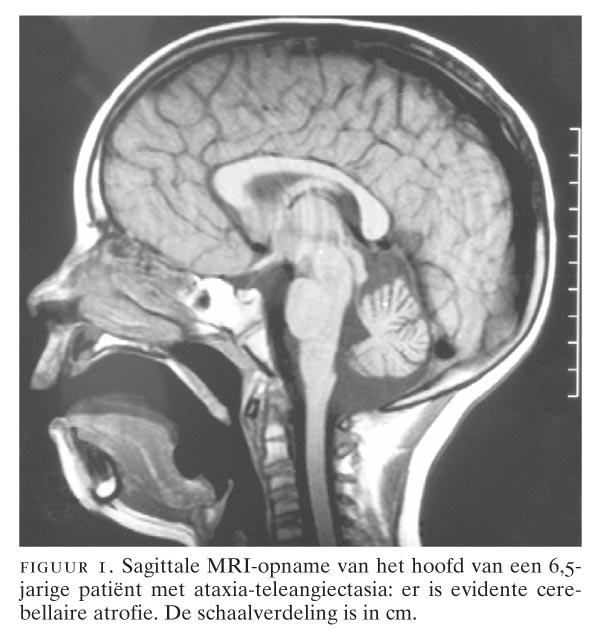

Cerebellaire ataxie is een essentieel kenmerk en begint meestal op de peuterleeftijd. De meeste patiënten zijn rolstoelafhankelijk vanaf ongeveer het 10e levensjaar. MRI-onderzoek van het cerebrum toont dan ernstige cerebellaire atrofie (figuur 1). Andere neurologische verschijnselen zijn choreoathetose, dystonie, oculomotorische dyspraxie en, in een latere fase van de ziekte (rondom het 20e levensjaar), polyneuropathie en spinale spieratrofie. De intelligentie is meestal normaal.